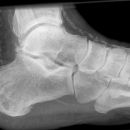

Calcaneus